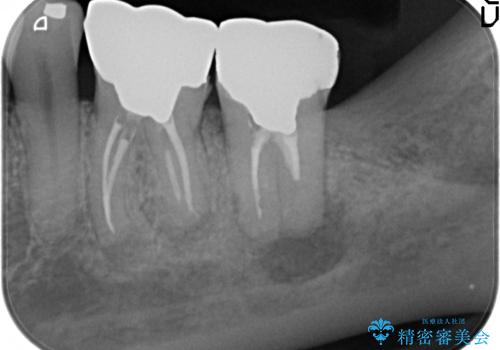

- 左下の奥歯が激しく痛むので診て欲しいといらっしゃった方の症例です。

左下7番目の歯に根尖病変を認めたため、再根管治療を行いました。

症状の消失を確認後、オールセラミッククラウンによる補綴を行いました。